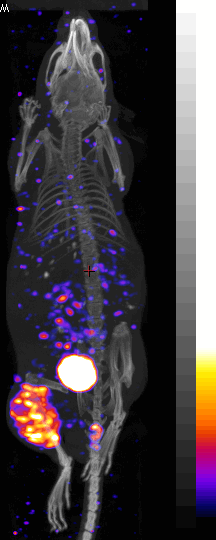

[64Cu] labeled Peptide tumor image

99mTc labeled oligomer |